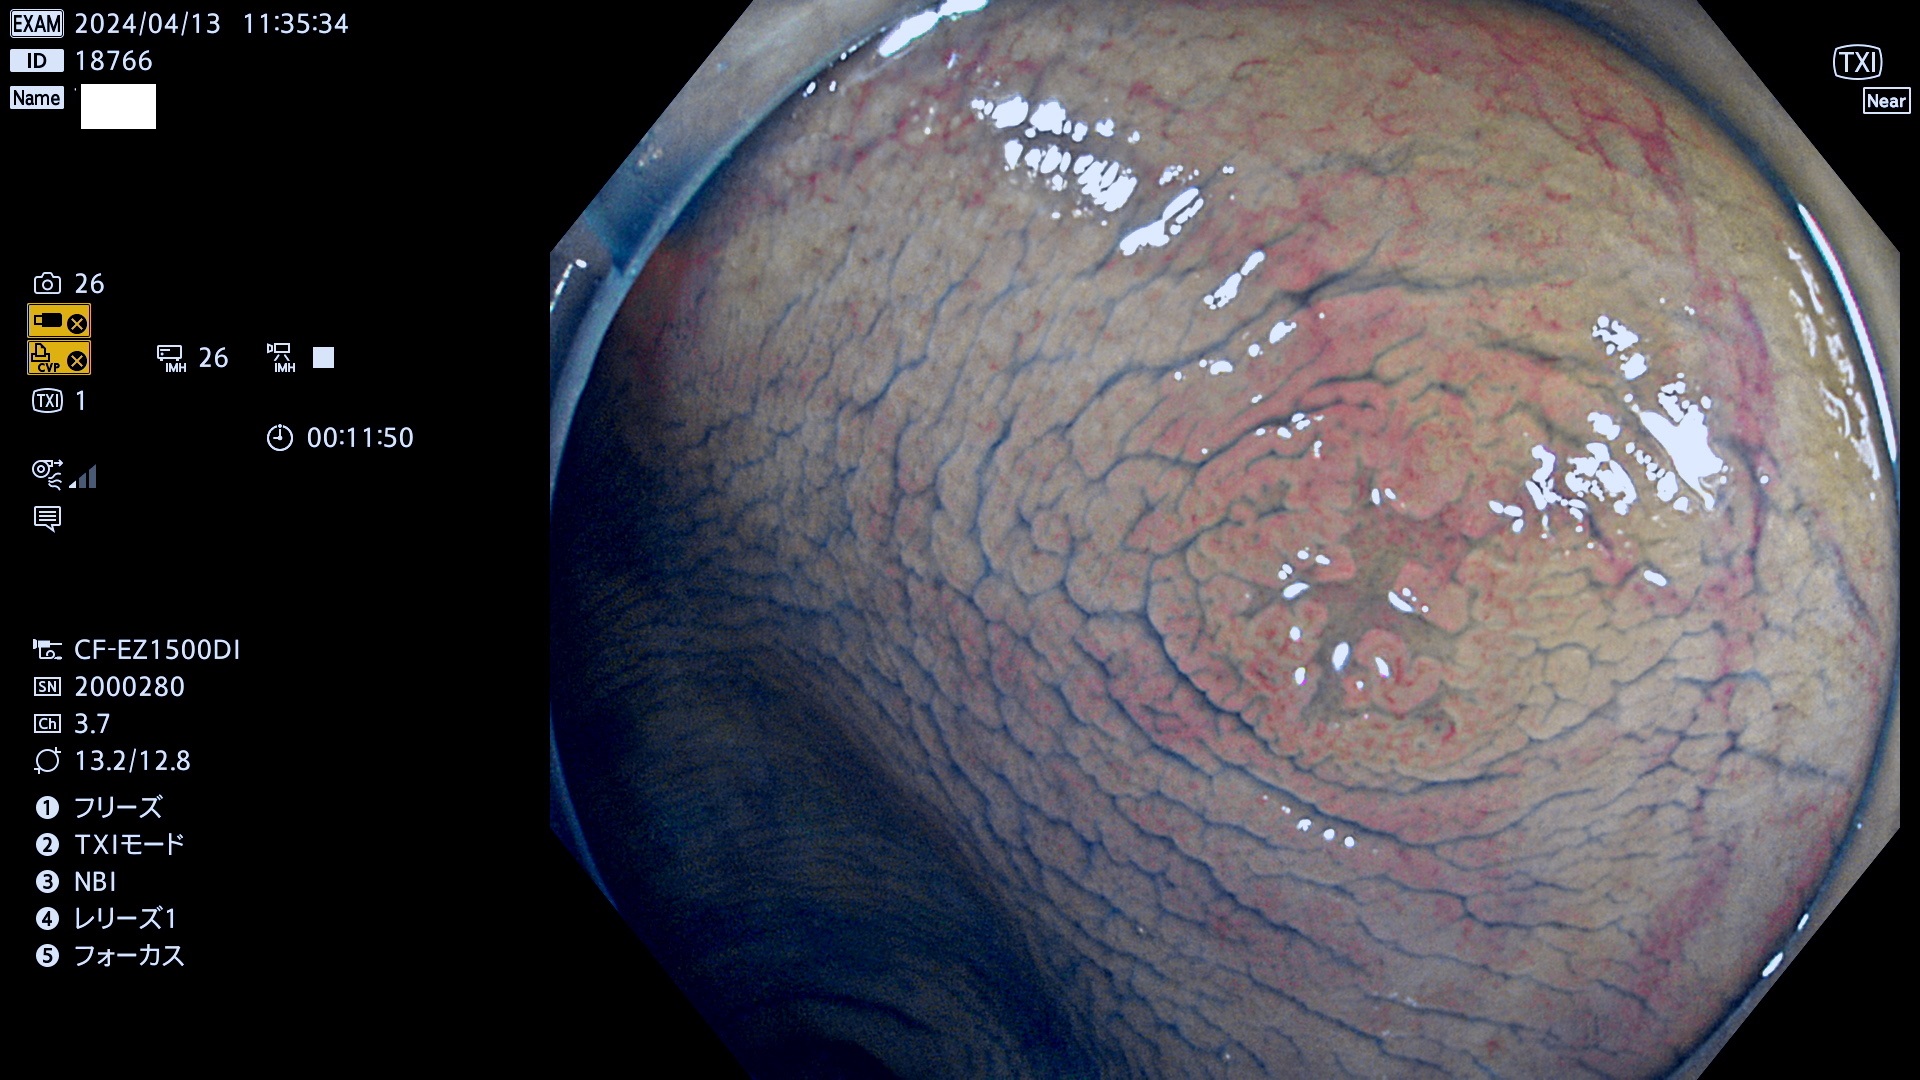

今週のUb、Uc型腺腫

表面型腺腫(Flat Adenoma)の中で、完全に平坦な物をUb、陥凹している物をUcと呼びます。平坦隆起型(Ua)よりも、発見が難しく危険な病変です。

専門的)Uc=De Novo癌? 内視鏡の解像度が低かった時代、このような説もありました。しかし今日の高精度内視鏡では良性の微小なUc型腺腫が日常的に見つかります。私見ですが「Ucこそが多段階発癌(Adenoma-Carcinoma Sequence)のMain Route」と考えます。

毎週の検査(木・金・土・日)に発見されたUb、Uc型・腺腫を、その週の日曜の夜にUPし1週間、提示します。

抽出の対象期間 2024年4月11日〜4月14の4日間(40件の検査)3件 (3/40=8%)